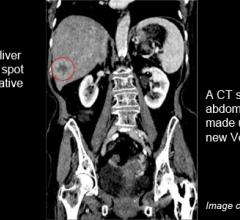

June 8, 2012 — The overwhelming majority (93.8 percent) of patients undergoing computed tomography (CT) of the abdomen and pelvis (CTAP) in the emergency department (ED) setting are classified as clinically complex, according to a study in the June issue of the Journal of the American College of Radiology. Clinically complex is used to describe patients who are, based on documentation of their ED physician, much sicker than others.